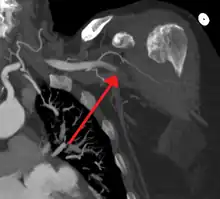

| Acute embolism to the right femoral artery resulting in ischemia | |